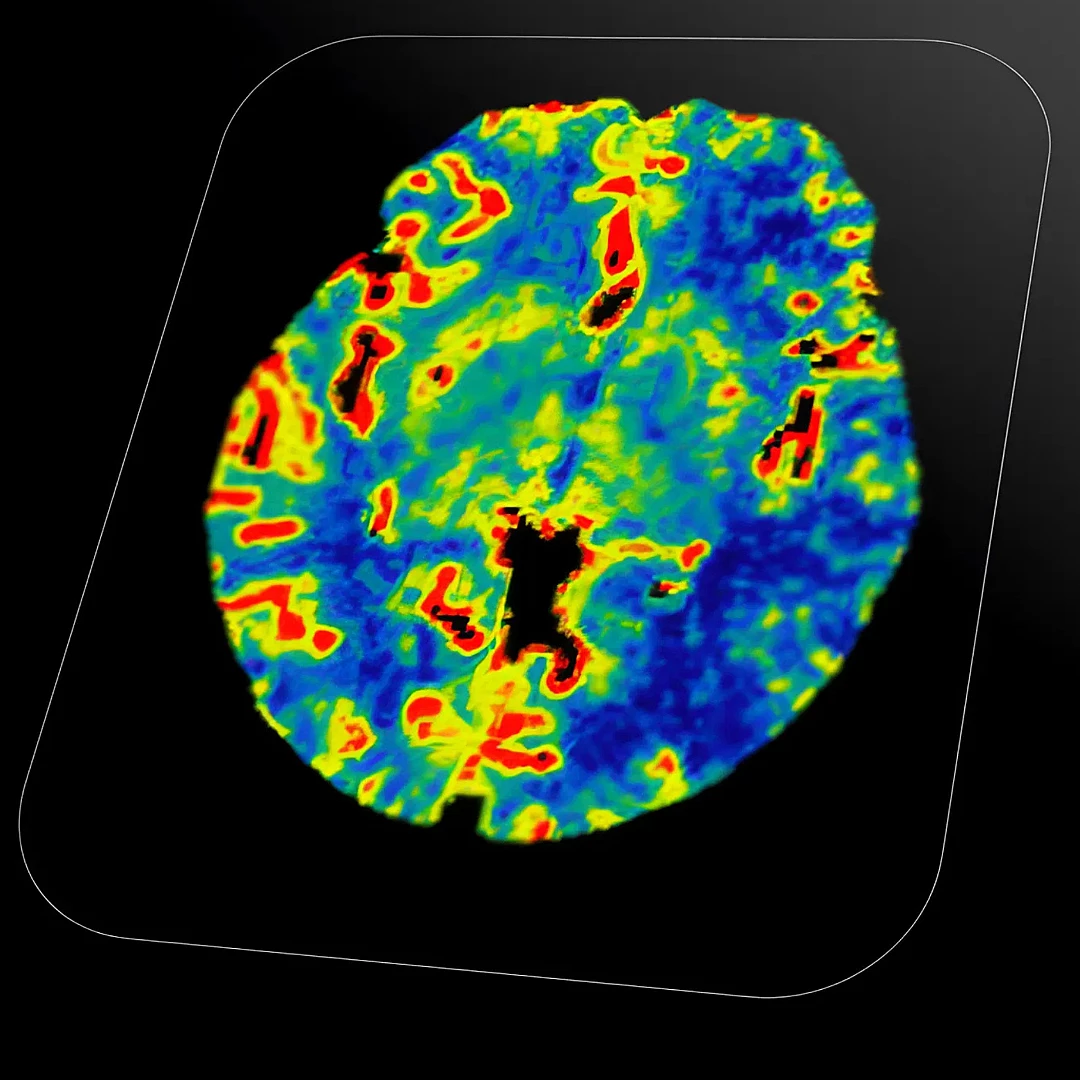

Stroke & Perfusion Brain MRI

Stroke and Perfusion Brain MRI evaluates blood flow in the brain to identify areas affected by stroke or reduced perfusion. It helps determine the extent of brain damage and guides timely, targeted treatment.